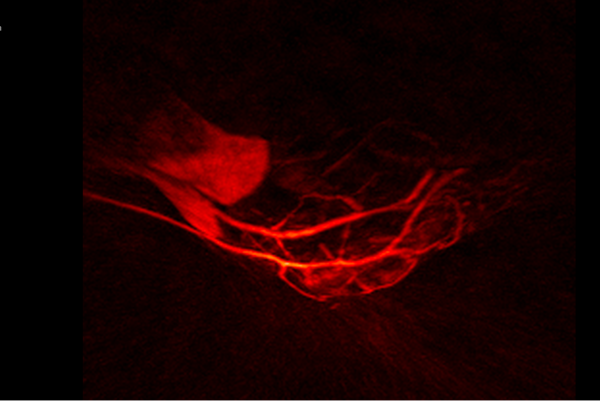

Nexus 128 transformed the way lab researchers can gather data. Using near-infrared light and a hemispherical shape, Nexus 128 captures more visual detail and a fully 3D picture, delivering clearer information to researchers.

Our Nexus 128 system is the first commercially available fully 3D photo-acoustic imaging system, providing increased sensitivity, isotropic resolution, improved image quality, faster scan times and higher throughput for imaging anatomy, physiology and labeled molecular targets.